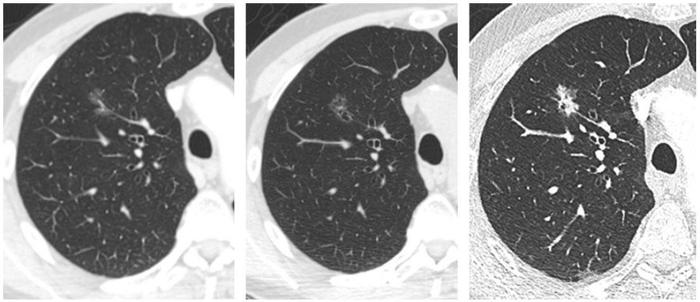

混合磨玻璃结节,伴有胸膜牵拉——肺腺癌